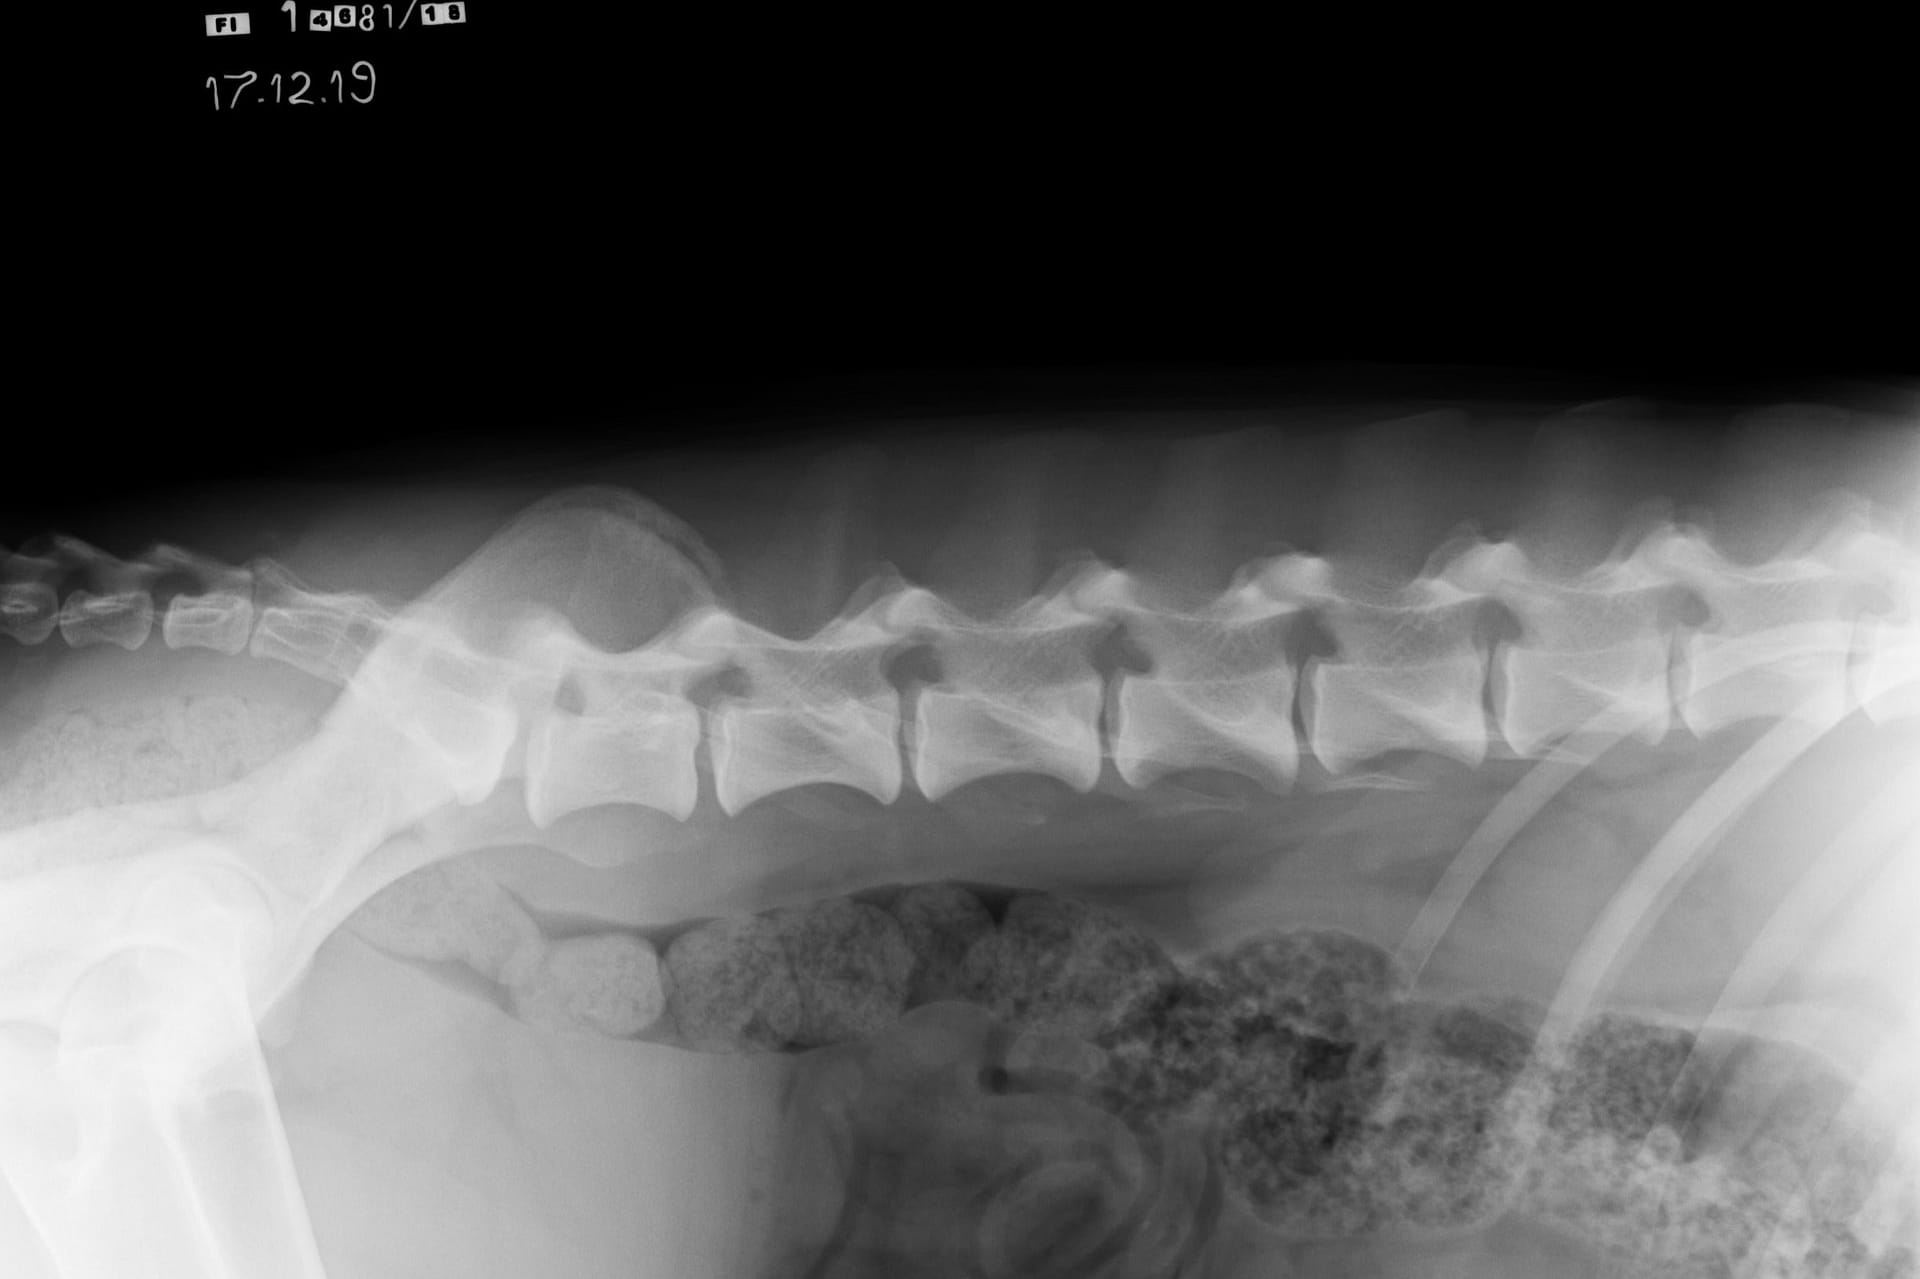

LTV4; 8 lumbar vertebras. L8 shaped like a lumbar vertebra and it has complete spinous process.